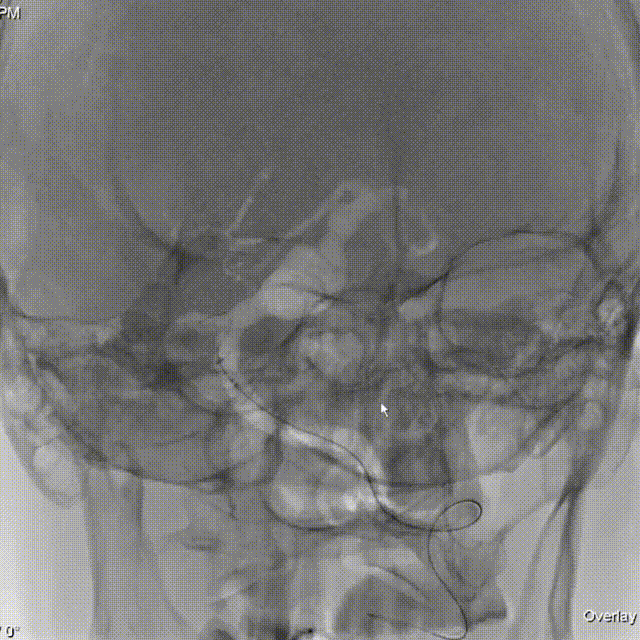

术后即刻造影:

术前影像资料